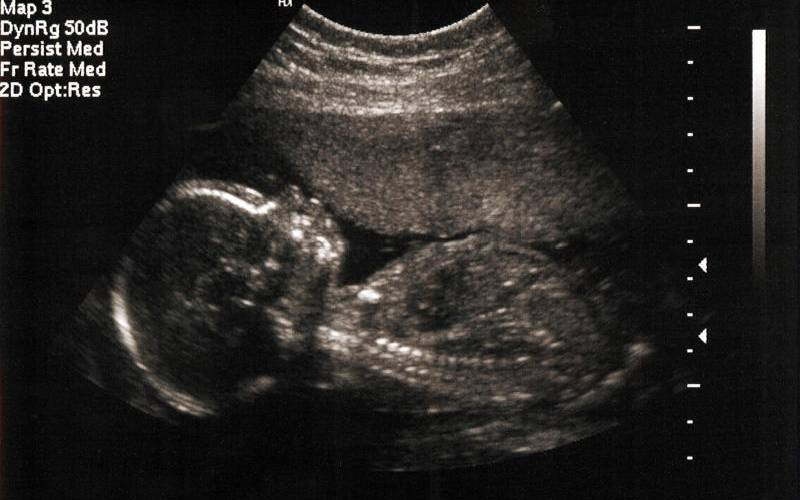

Once stillbirth is suspected, diagnosis is confirmed through ultrasound to check for the baby’s heartbeat. If confirmed, families are given space to grieve and make decisions about the delivery. Labour is usually induced, though some may choose to wait for it to begin naturally. A Caesarean section might be necessary in some cases, especially if there are medical complications like heavy bleeding.